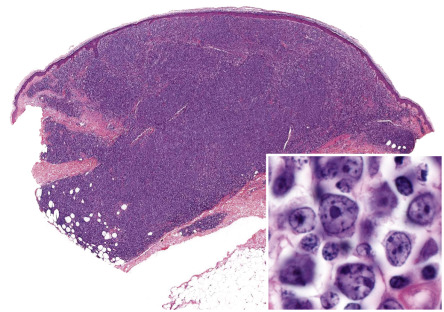

In DLBCLLT, a dense diffuse infiltrate is seen within the dermis and subcutis. The infiltrate usually involves the entire papillary dermis extending to the dermal–epidermal junction. Involvement of the epidermis by clusters of large atypical cells, simulating the Pautrier microabscesses found in cutaneous T-cell lymphoma, can be observed in some cases (B-cell epidermotropism), representing a potential diagnostic pitfall . The neoplastic infiltrate consists predominantly of immunoblasts (large round cells with abundant cytoplasm and prominent nucleoli) and centroblasts ( Fig. 119.11 ). Of note, cases of pCBCLs with a predominance of large cleaved cells (i.e. large centrocytes) are classified among the PCFCLs (see above) . Reactive small lymphocytes are usually few in number, and mitoses are frequent. The common finding of immunoglobulin gene hypermutations is evidence that DLBCLLT is a large cell lymphoma, representing post germinal center lymphocytes that originated from lymphocytes of the germinal center.

Neoplastic cells are positive for B-cell markers (CD20, CD79a, PAX-5, IgM), but there can be (partial) loss of antigen expression. Bcl-2, MUM-1 (see above), FOX-P1, and MYC are expressed by neoplastic cells in most patients . These markers are useful in the differential diagnosis of DLBCLLT from PCFCL, diffuse type; in the latter, Bcl-2, MUM-1, and FOX-P1 are usually either negative or expressed by a small minority of cells ( Fig. 119.12 ). The tumors demonstrate monoclonal rearrangement of IGH . The interchromosomal 14;18 translocation is not present. An algorithmic approach to the diagnosis of cutaneous diffuse large B-cell lymphomas is provided in Fig. 119.13 . The differential expression of lymphoid markers in various types of diffuse large B-cell lymphoma with cutaneous involvement is summarized in Table 119.3 .